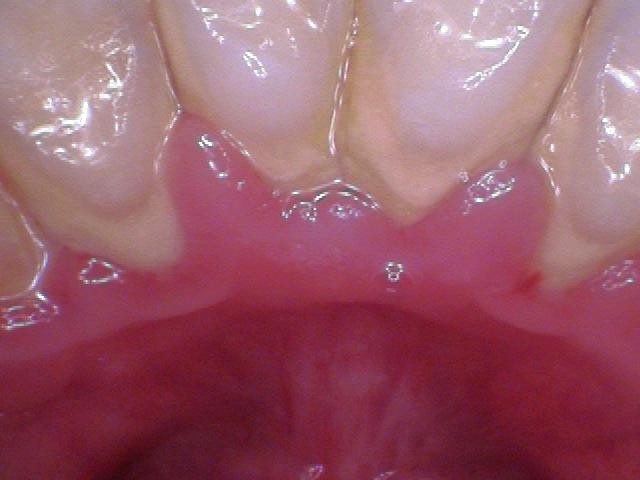

Shown above is gum disease in early to moderate stages. The red lines indicate pocketing around the teeth and the red dots indicate an active infection (bleeding).